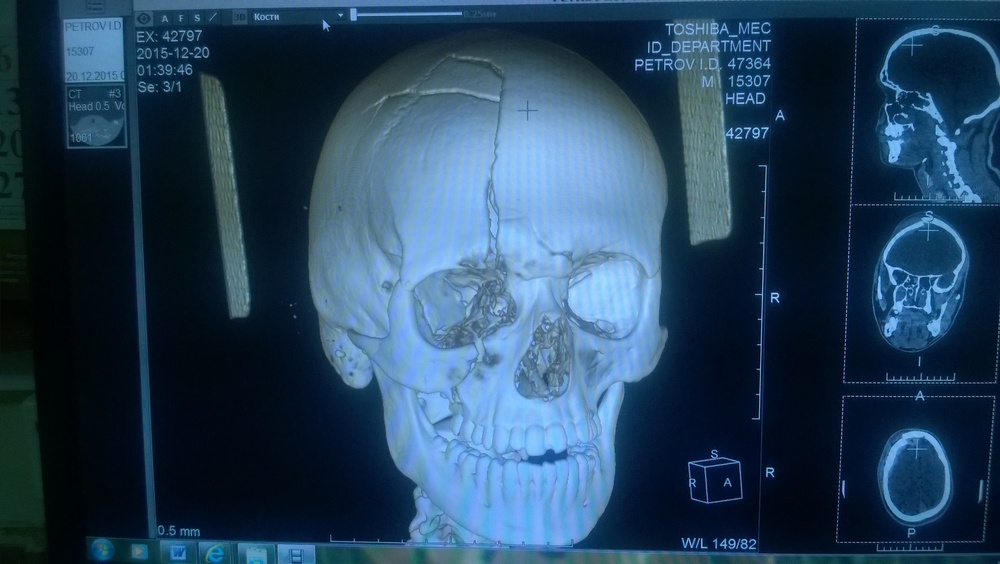

На волне постов о самочувствии после наркоза вспомнились и мои впечатления от данной процедуры. По несчастливой случайности в июле этого года попал в аварию. Весь удар пришелся на голову, 4 перелома в черепе + рассечения и прочие неприятности. Остальные части тела отделались царапинами и ушибами. На скорой привезли в больницу, сделали тут же компьютерную томографию. Вот такой результат я увидел на снимках

Дело было часов в 5 утра, я уснул только зайдя в палату (что удивительно, ибо боль была довольно сильной). Около 8-ми утра меня растолкали и повезли оперировать лобную кость (открытый перелом, надо было ставить на место). Волнения не было, хоть и на операционный стол положили впервые в жизни. Пока шла подготовка я обратился к ассистентке хирурга: